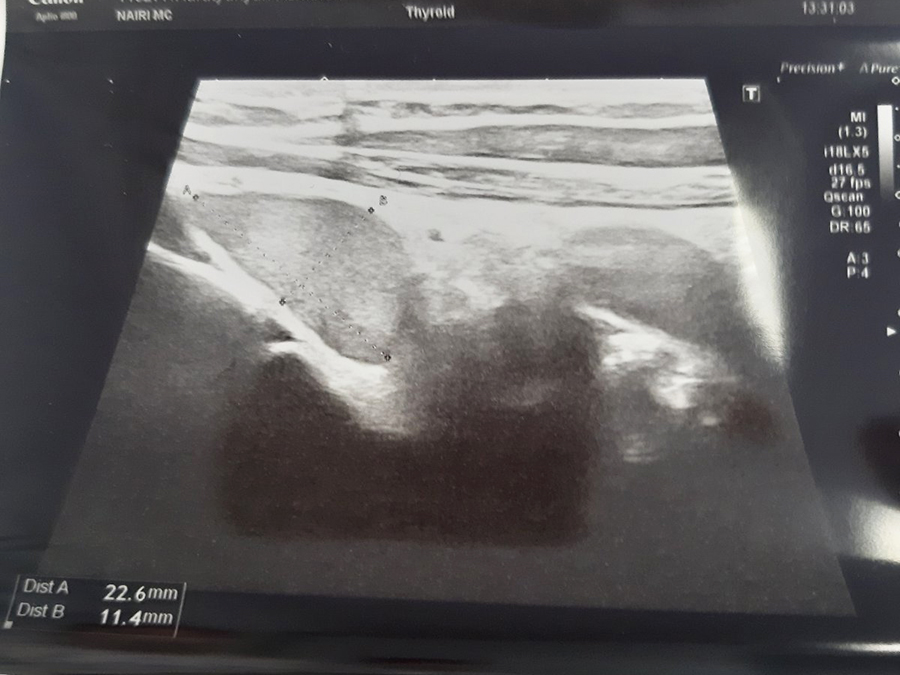

«Նաիրի» ԲԿ ընդունարան էր դիմել 30 տարեկան կին` ոսկրային համակարգի քաղցկեղի կասկածով: Ուղղորդվել էր օնկոօրթոպեդի մոտ, ով պետք է իրականացներ բաց բիոպսիա` ախտորոշման հաստատման համար: Սակայն երկարատև զննումից, մանրամասն անամնեզ հավաքելուց հետո օնկոօրթոպեդի մոտ առաջացավ կասկած, որ պացիենտի մոտ առկա է հարվահանաձև գեղձի հետ կապված խնդրով պայմանավորված օստեոպորոզ: Գործընթացին միացավ էնդոկրին վիրաբույժը, կատարվեց ՈՒՁ հետազոտություն, պարանոցի և կրծքավանդակի համակարգչային տոմոգրաֆիա, ինչի արդյունքում հայտնաբերվեց աջ ստորին հարվահանագեղձի բավականին մեծ չափերի` մոտավորապես 25 մմ ադենոմա, որից հետո պացիենտին նախապատրաստեցին և կատարեցին վիրահատություն. հեռացվեց ախտահարված հարվահանագեղձը:

Վիրահատությունը տևեց բավականին կարճ, հարթ ընթացքով, առանց բարդությունների: Պարաթիրեոիդէկտոմիայից 30 րոպե անց կատարվեց արյան մեջ պարաթհորմոնի կրկնակի քննություն, որն արդեն իսկ մոտեցել էր նորմային: Թվերի տեսքով ներկայացնելիս, ցուցանիշը` 528-ից դարձել էր 83:

Վիրահատության հաջորդ օրը կալցիումն արյան մեջ նույնպես արդեն նորմայի սահմաններում էր, որը նախքան վիրահատությունը նույնպես շատ բարձր էր: Երկու շաբաթ անց կատարված հետազոտությունների արդյունքները նորմայի սահմաններում էին (պարաթհորմոնը, կալցիումը): Պացիենտը նշում էր ոսկրային ցավերի խիստ նվազում: